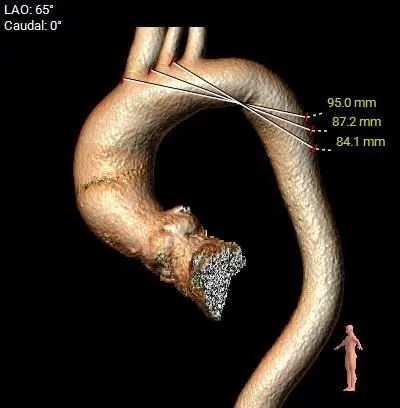

Type 1型二叶式主动脉瓣,右无融合,重度钙化,钙化分布不均匀,无窦和左窦瓣叶钙化较重呈长条块状,右冠窦内钙化向左室流出道衍生,无窦和右窦瓣叶对合缘处存在钙化嵴,左窦和右窦瓣叶对合缘处存在局部钙化黏连,瓣叶对合缘处存在增厚及钙化粘连。

瓦氏窦内径尚可,窦管交界内径尚可、升主动脉内径可,左室腔内径尚可、心室壁增厚,左室流出道呈敞口形态。

主动脉瓣环水平夹角47度,非横位心,主动脉弓宽度、角度可,弓部存在少量散在钙化。

外周走行存在多处迂曲,腹主上端和左侧髂总动脉存在少量散在钙化斑,血管内径可,血管内壁存在钙化和不规则纤维增厚。

考虑右侧股动脉为主入路,左侧为辅助入路。右冠窦内钙化向左室流出道衍生,左室流出道呈敞口形态,非横位心,弓部存在少量散在钙化,预估输送器过弓与跨瓣顺利。瓣叶冗长,CT提示右冠脉显影不佳,建议术前行冠脉造影进一步评估冠脉风险。外周走行可见多处迂曲,需注意小心通过。由于Type1型二叶式主动脉瓣伴瓣叶长条块状重度钙化,瓣口限制明显,手术预装AV26备AV23瓣膜,根据20mm球囊预扩结果选择瓣膜型号,计划瓣膜释放定位深度接近瓣环。